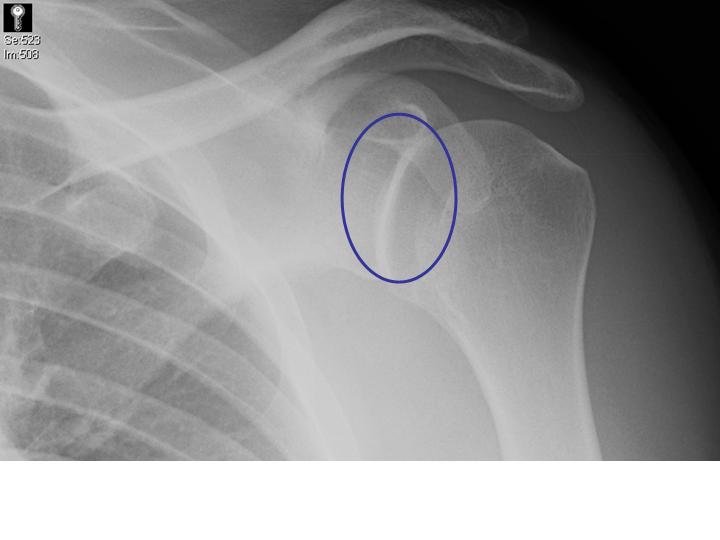

Adequate radiographs are essential for diagnosis and associated fractures, which are common. Posterior shoulder dislocations may appear deceptively normal on AP or Grashey views.

- The normal elliptically-shaped overlap of the humeral head and the glenoid may be absent in posterior shoulder dislocations.

- The articulation may be mistaken as normal, but part of the glenoid may actually be vacant, the so called "rim sign."

The patient's AP film (left) shows an abnormal glenohumeral articulation (no elliptical glenohumeral overlap)without a "rim sign" or "cystic" humeral head.